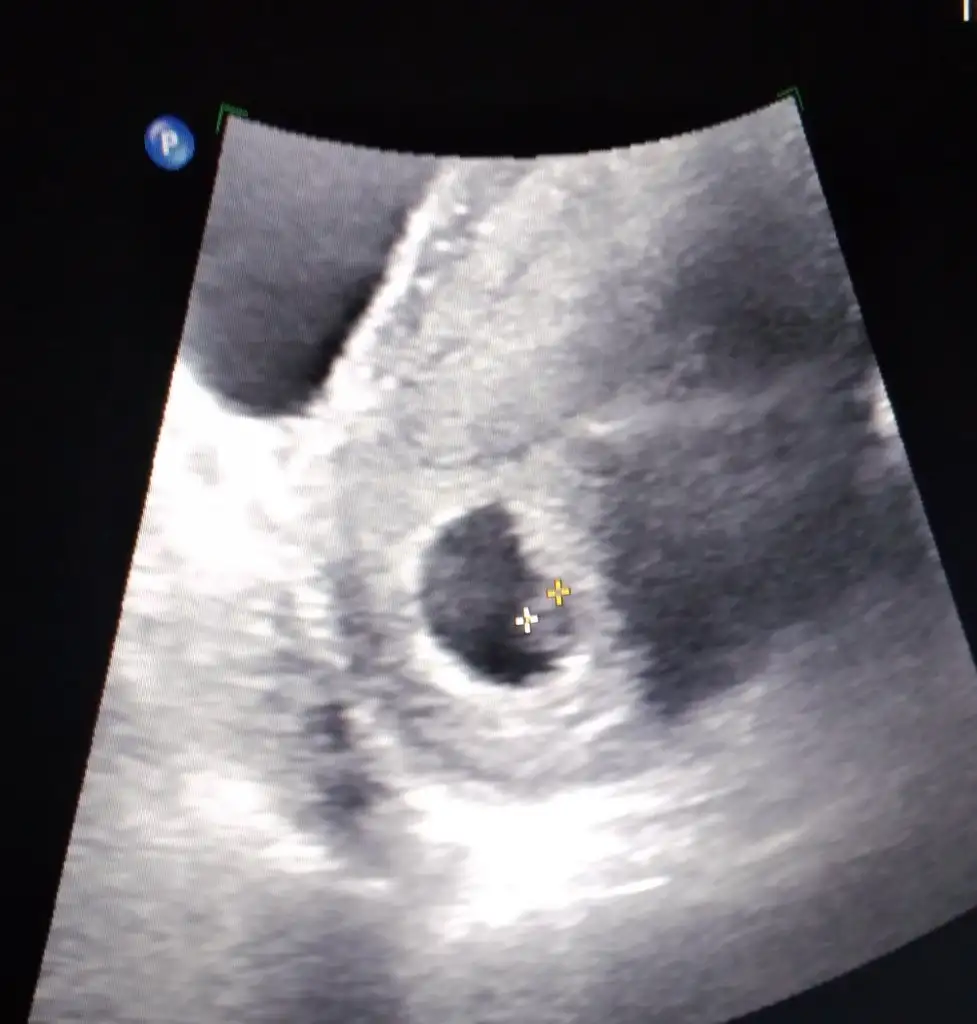

Cevaplarsaniz sevinirim. 7 haftalik karindan.